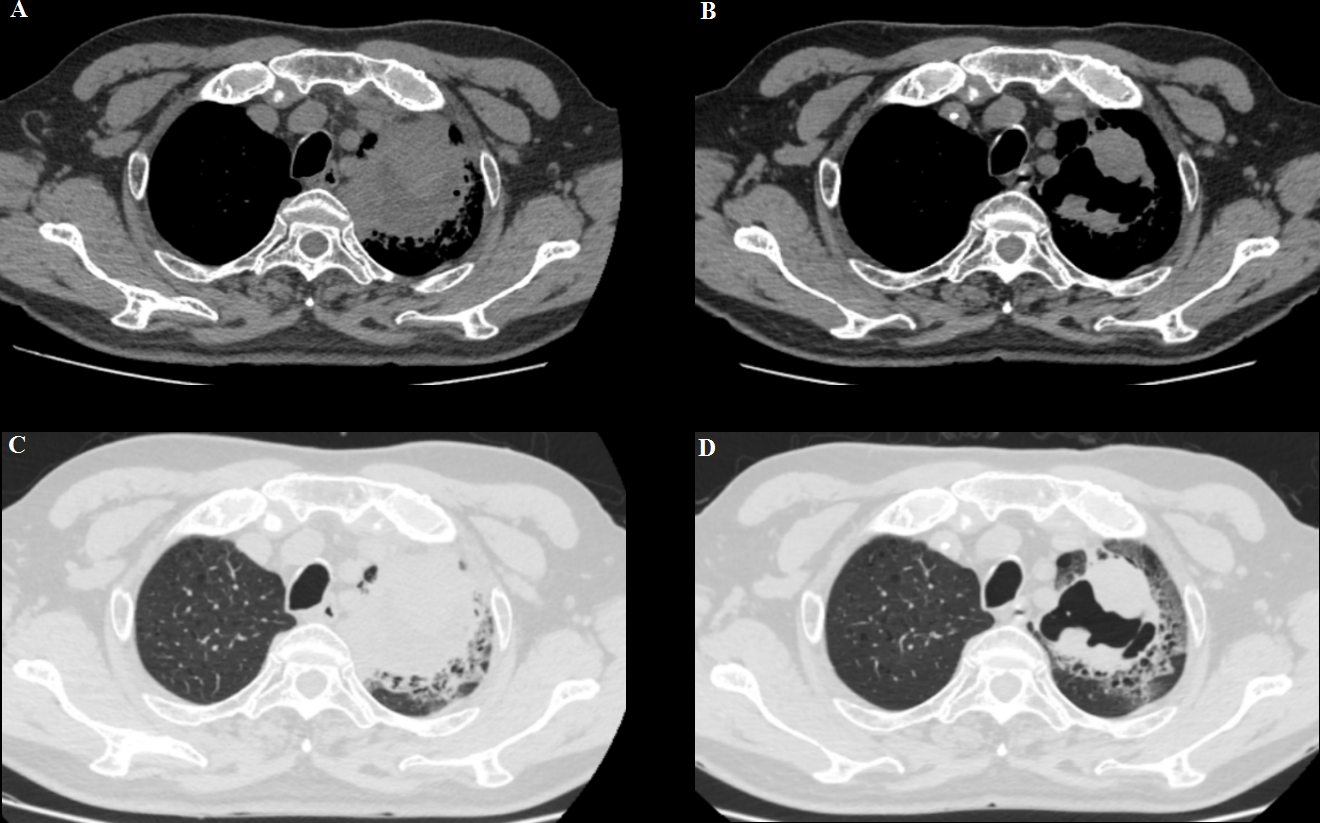

Meanwhile, the patient’s respiratory symptoms improved after immunotherapy. At 5 weeks of follow-up, the left lung mass showed partial response (PR) and became an irregularly cave on a computed tomographic scan (Figure 2). However, the patient repeatedly developed complications such as pneumonia, heart failure, blood glucose instability, and type II respiratory failure due to the complexity of his underlying disease and was treated with prolonged courses of antibiotics; thus, he could not be treated with anti-tumor therapy.

Figure 2

(A, C) A baseline computed tomography scan taken before treatment with ICI therapy, demonstrating the left lung mass. (B, D) A computed tomography scan taken at the time of BP development (6 weeks after pembrolizumab discontinuation), showing a partial response.